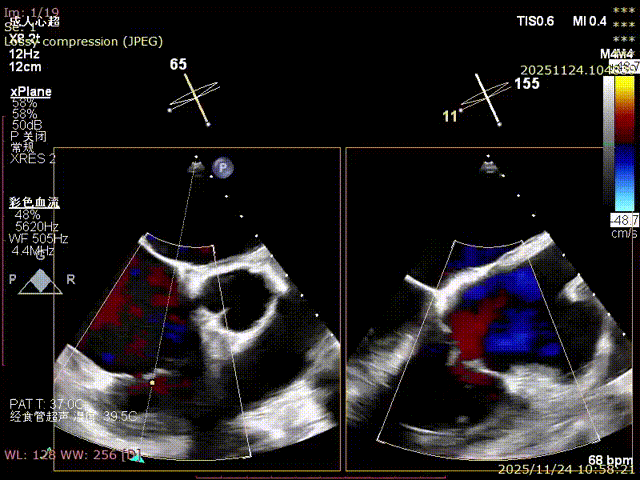

During the procedure, close collaboration was maintained with Dr. Yang Yan (anesthesiologist, Department of Anesthesiology) and Dr. Niu Ming (echocardiography specialist, team of Director Zhai Hong, Department of Cardiac Ultrasound). Guided by transesophageal echocardiography and assisted by DSA imaging, the tricuspid annular structure and regurgitation jet direction were precisely assessed. Ultimately, two 12T K-Clip® devices were successfully implanted. Immediate postoperative echocardiographic evaluation showed a significant reduction in tricuspid regurgitation from 4+ preoperatively to 1+, with a marked decrease in annular area. The surgical outcome was satisfactory.

Echocardiographic: Severe tricuspid regurgitation (grade 4+), with the regurgitant jet mainly located at the posteroseptal and central regions. No significant dilatation of the tricuspid annulus is observed. Mild myxomatous degeneration of the tricuspid leaflets is present, showing Barlow-like morphology, with leaflet prolapse of 3.7 mm in height.